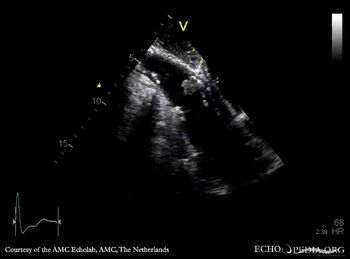

A4CH: concentric hypertrophy of left ventricle A3CH with Color Doppler: high velocity transaortic flow, mild aortic regurgitation